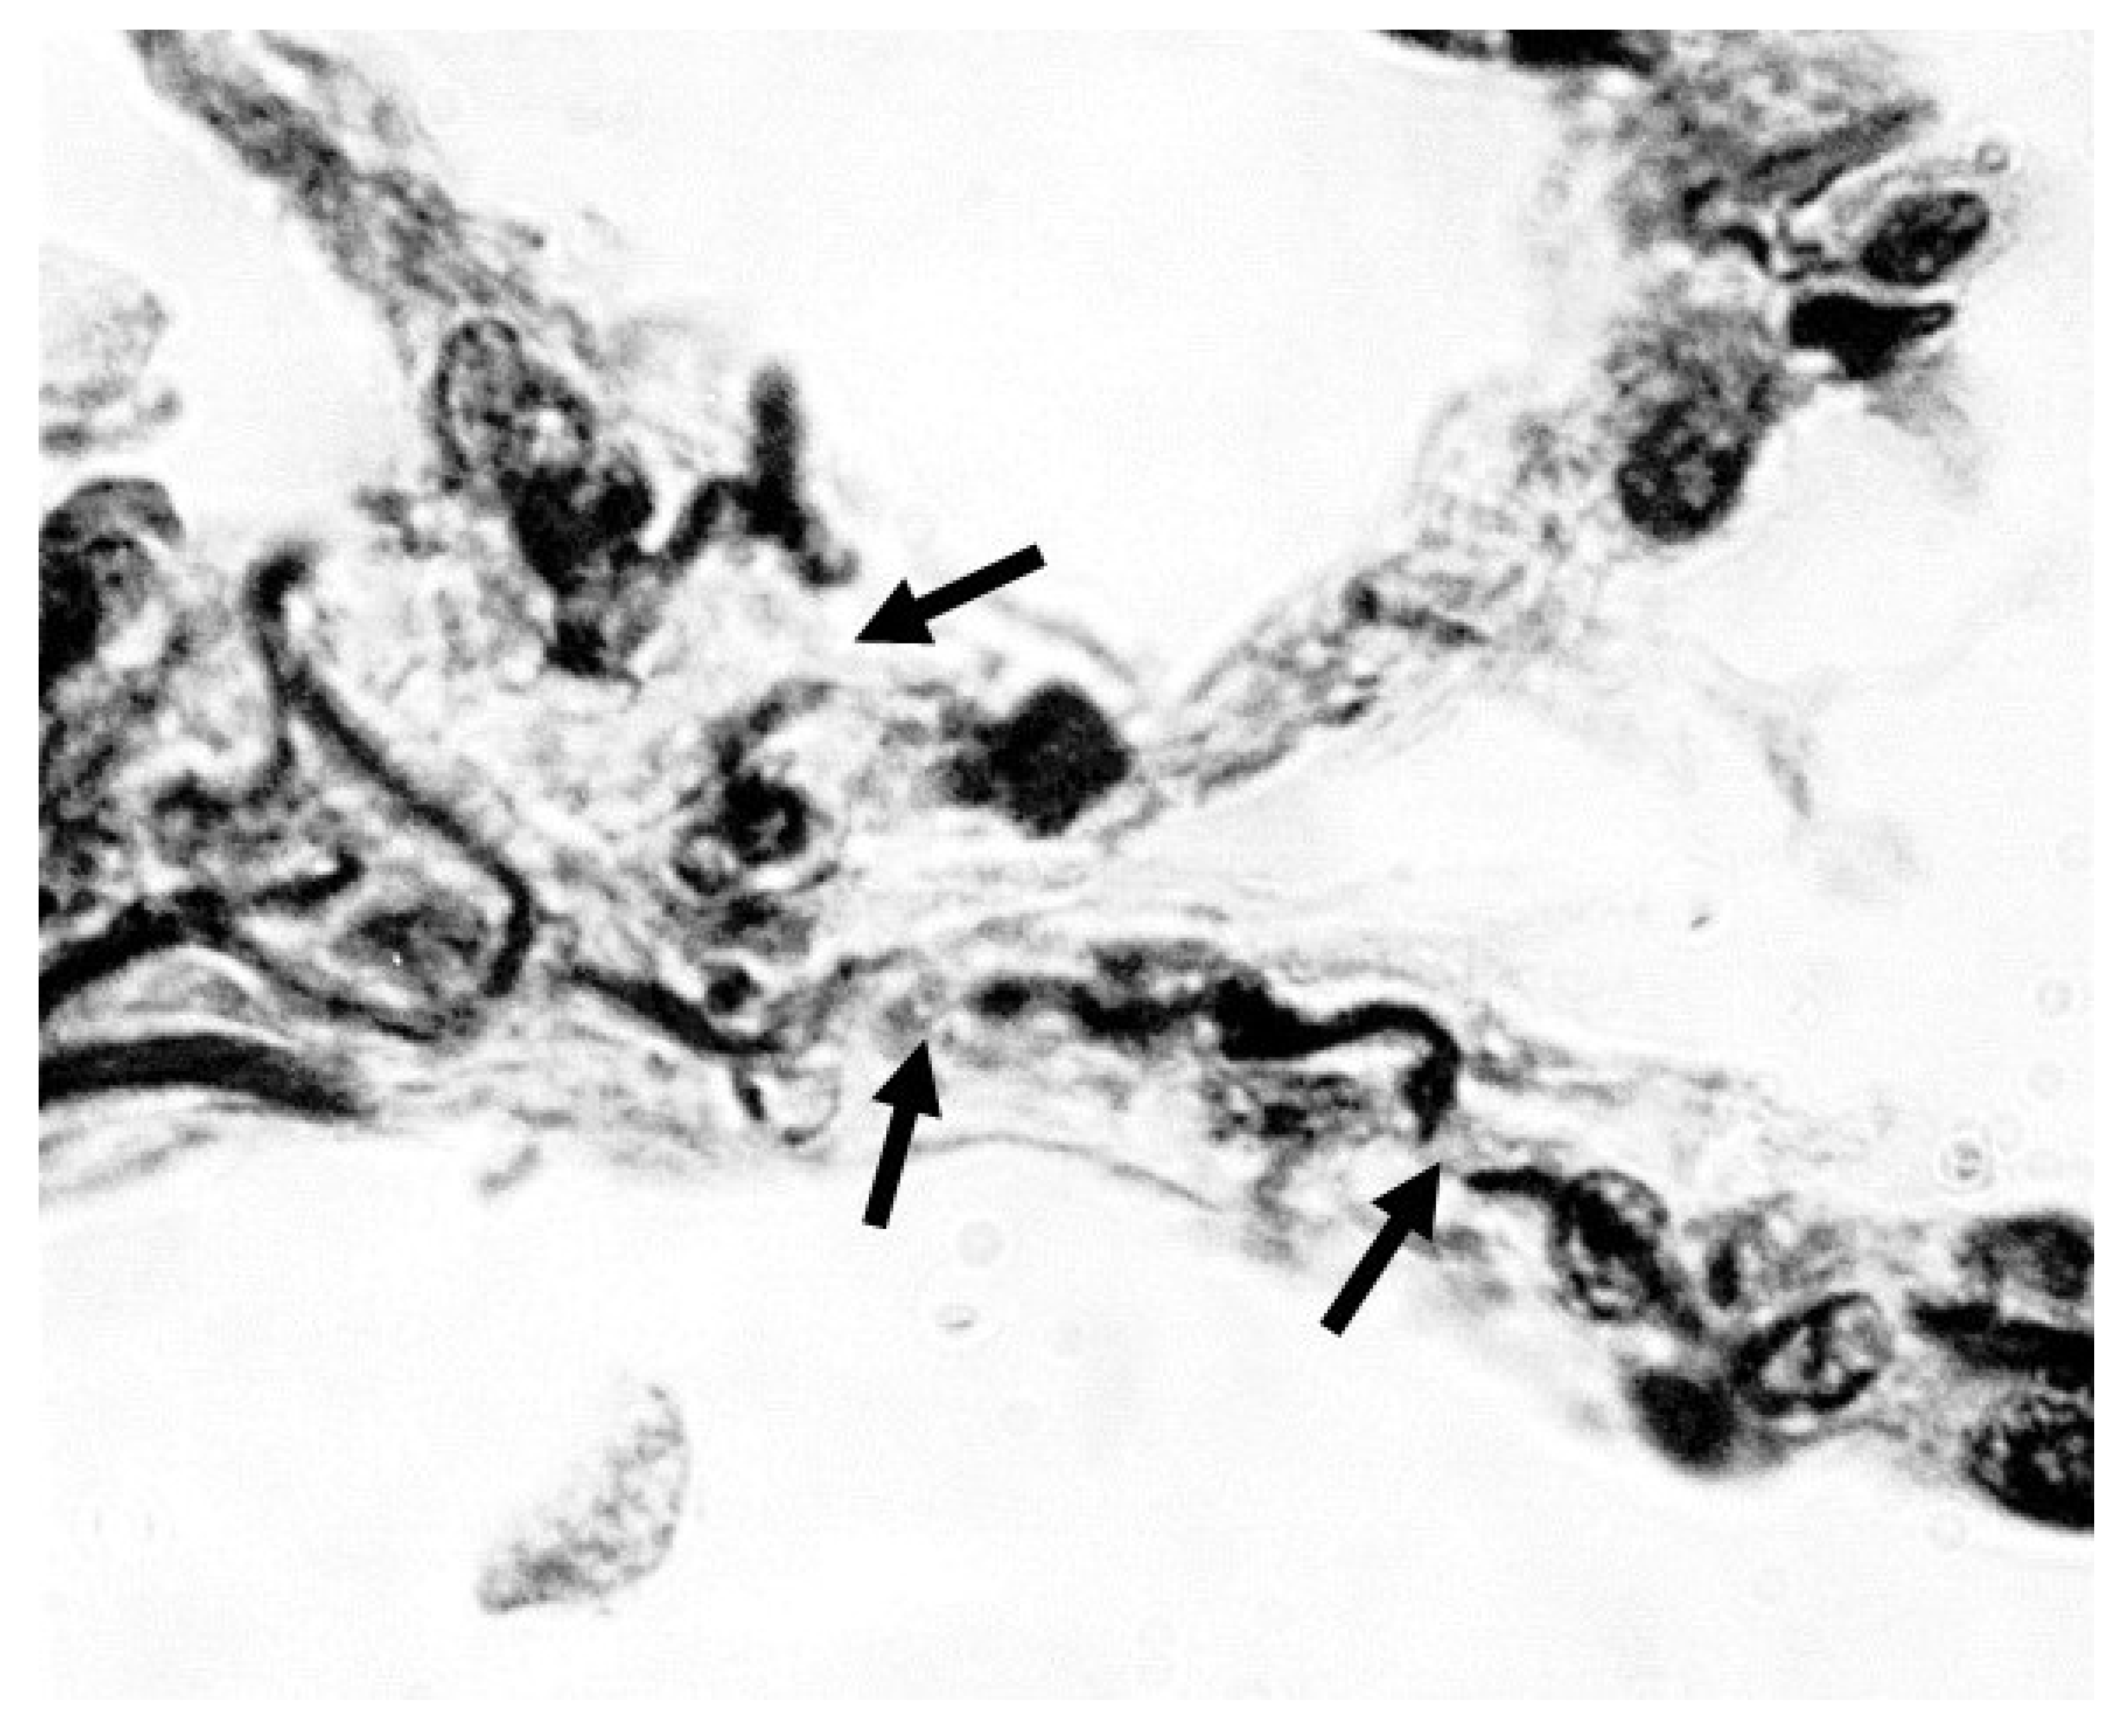

Figure 1. Photomicrograph showing fragmented elastic fibers (arrows) in alveolar walls of a human postmortem lung with moderate pulmonary emphysema. Orcein stain; 1000x magnification. Reprinted with permission (11).

The nonlinear progression of disease may be modeled using percolation theory, where fluid movement through a network of interconnected channels represents the progression of chemical and physical phenomena (12). Regarding the lung, the percolation of mechanical forces through the elastic fiber network represents an analogous process, in which the fragmentation of elastic fibers resembles the random disconnection of percolation bonds (Figure 1). A phase transition occurs when a critical threshold is reached, involving a widespread loss of connectivity that results in uneven transmission of mechanical forces and the emergence of clinically apparent disease (13). This transition may be manifest by changes in lung compliance and gas exchange.